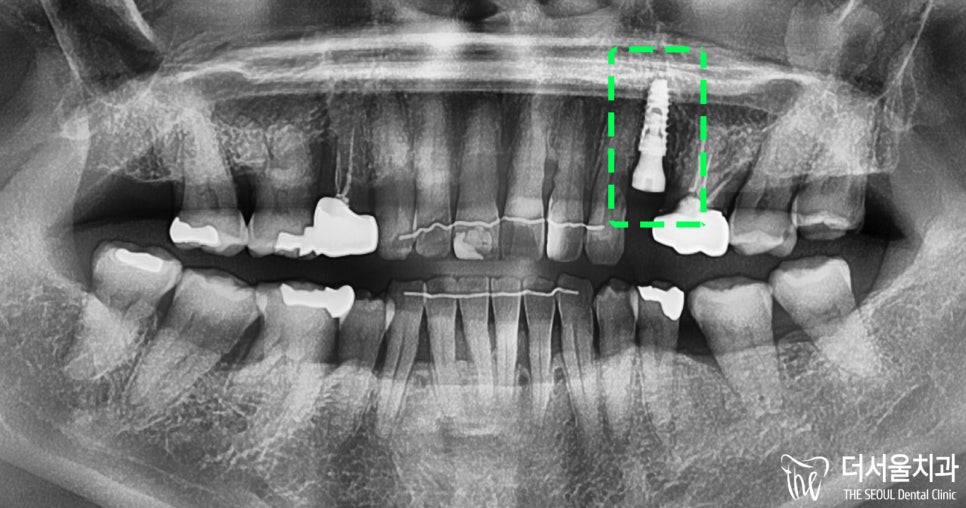

3. 결과

가이드를 이용하여 수진동 임플란트를 심은 결과입니다.

올바른 위치에 잘 식립된 것을

파노라마 엑스레이 촬영으로

확인할 수 있습니다.